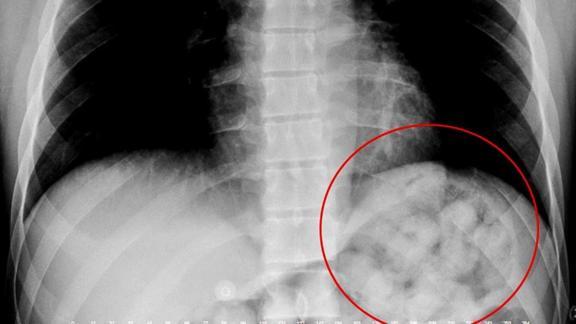

Sabiha Gökçen Havalimanı'nda görevli gümrük muhafaza ekiplerince, 27 Şubat'ta Katar'ın başkenti Doha'dan uçakla gelen Surinam uyruklu B.T.M'nin yapılan kontrolünde, midesinde 82 kapsülde toplam 1 kilo 180 gram uyuşturucu tespit edildi.

Şüpheli B.T.M. savcılıktaki ifadesinde, uyuşturucuyu Brezilya'da yuttuğunu, sonra Sao Paulo'dan Doha'ya, oradan da İstanbul'a geldiğini anlatarak, "Türkiye'de bunları doğal yolla çıkarıp İstanbul'da sokaklarda satacaktım. Burada iletişimde olduğum biri yok. 4 Mart için de Brezilya'ya dönüş biletim vardı. Taksim'de bir otelde rezervasyonum vardı. Otelin ücretini de uyuşturucuları sattığımda ödeyecektim. Suçlamaları bu halde kabul ediyorum." ifadelerini kullandı.